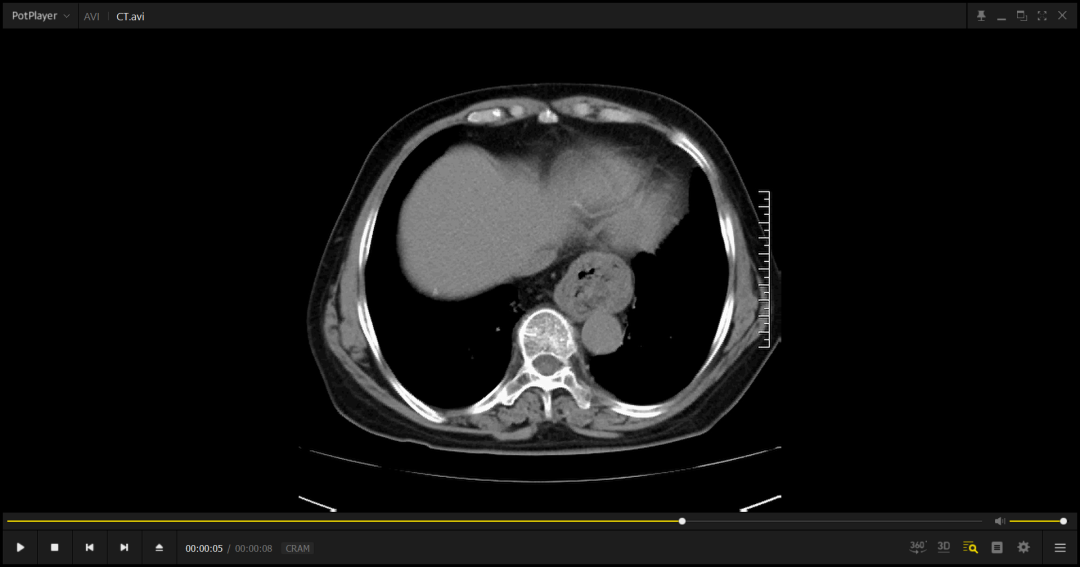

王女士五年来辗转多家医院,常规呼吸系统治疗始终无效。漯河市中心医院接诊后,通过胃镜、食道测酸、高分辨率CT等多维度检查,最终锁定"真凶"——食管裂孔直径达6cm的巨大缺损,导致胃组织疝入胸腔,长期胃酸反流刺激气道引发咳嗽。胃肠疝外科主任罗威指出:"约30%胃食管反流患者并无典型反酸症状,仅表现为慢性咳嗽、咽痛,且症状常在夜间平卧或摄入刺激性饮食后加重。"